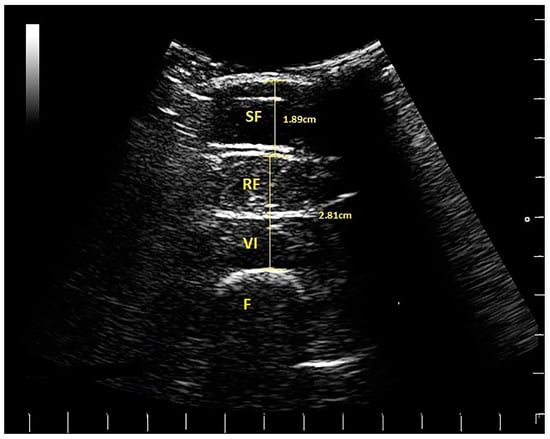

Participants rested while seated for a minimum of 10 minutes before the ultrasound images were taken. Images of the anterior thigh were produced using a real-time B-mode ultrasound scanner (Imagic Agile, Pie Data, Ltd., Kontron Medical, St Germaine en Laye, France) with a 5–6.6 MHz curvilinear (abdominal) transducer. The transducer was placed transversely at a point two-thirds of the distance between the anterior-superior iliac spine and the superior pole of the patella, which was marked on the skin with a non-toxic pen [18]. Participants lay relaxed in supine lying, with the knee extended and leg supported by sand bags on either side of the ankle to maintain the hip in neutral (Figure 1). The probe was placed on the skin, with minimal pressure, to produce an image showing rectus femoris (RF), vastus intermedius (VI), SF, and perimuscular fascia. Two images were taken from the dominant side by the same experienced operator (SB). Leg dominance was determined by the preferred leg for kicking a ball.

Images were measured later off-line by IH, using a Matlab algorithm (written by MW). The thickness of two tissue layers was measured: (1) the superficial non-contractile layer comprised subcutaneous fat and superficial fascia measured from the skin to the inferior border of the superficial fascial layer; (2) the contractile layer consisted of RF and VI muscles, including the deep fascia between them, measured from the inside edge of the superior border of RF to the inside edge of the inferior border of VI (Figure 2). These two measurements were a simplified version of the measurement protocol used by [4], which involved making separate measurements of subcutaneous fat, superficial, and deep fascia and muscle thickness; hence, scans from the earlier study were re-analysed using the modified protocol. Each image was measured twice, and the mean values were used in the analysis.

Figure 2. Ultrasound scan from a female golfer, indicating subcutaneous fat (SF), rectus femoris (RF), vastus intermedius (VI) and the femur (F). The scale on the right and bottom of the scan is in cm (white lines). The thickness of the tissues is indicated (SF = 1.89 cm) and muscle (RF plus VI = 2.81 cm).